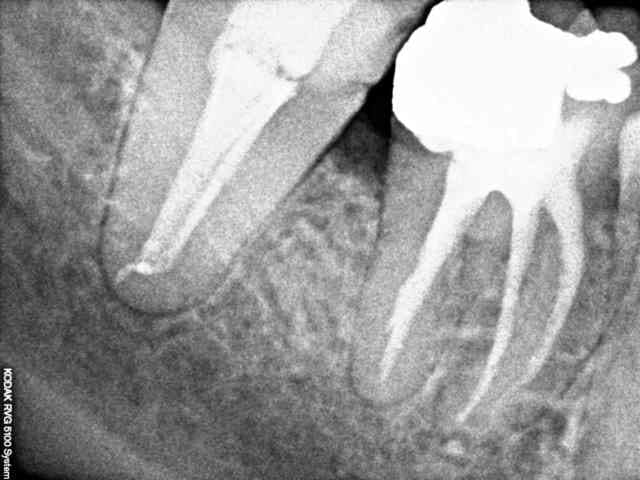

PS: J'ai mis la radio de la dent controlatérale un confrère n'avait visiblement pas mieux compris l'anatomie canalaire.

Un cas traite l'an dernier et pas de pb a ce jour ...